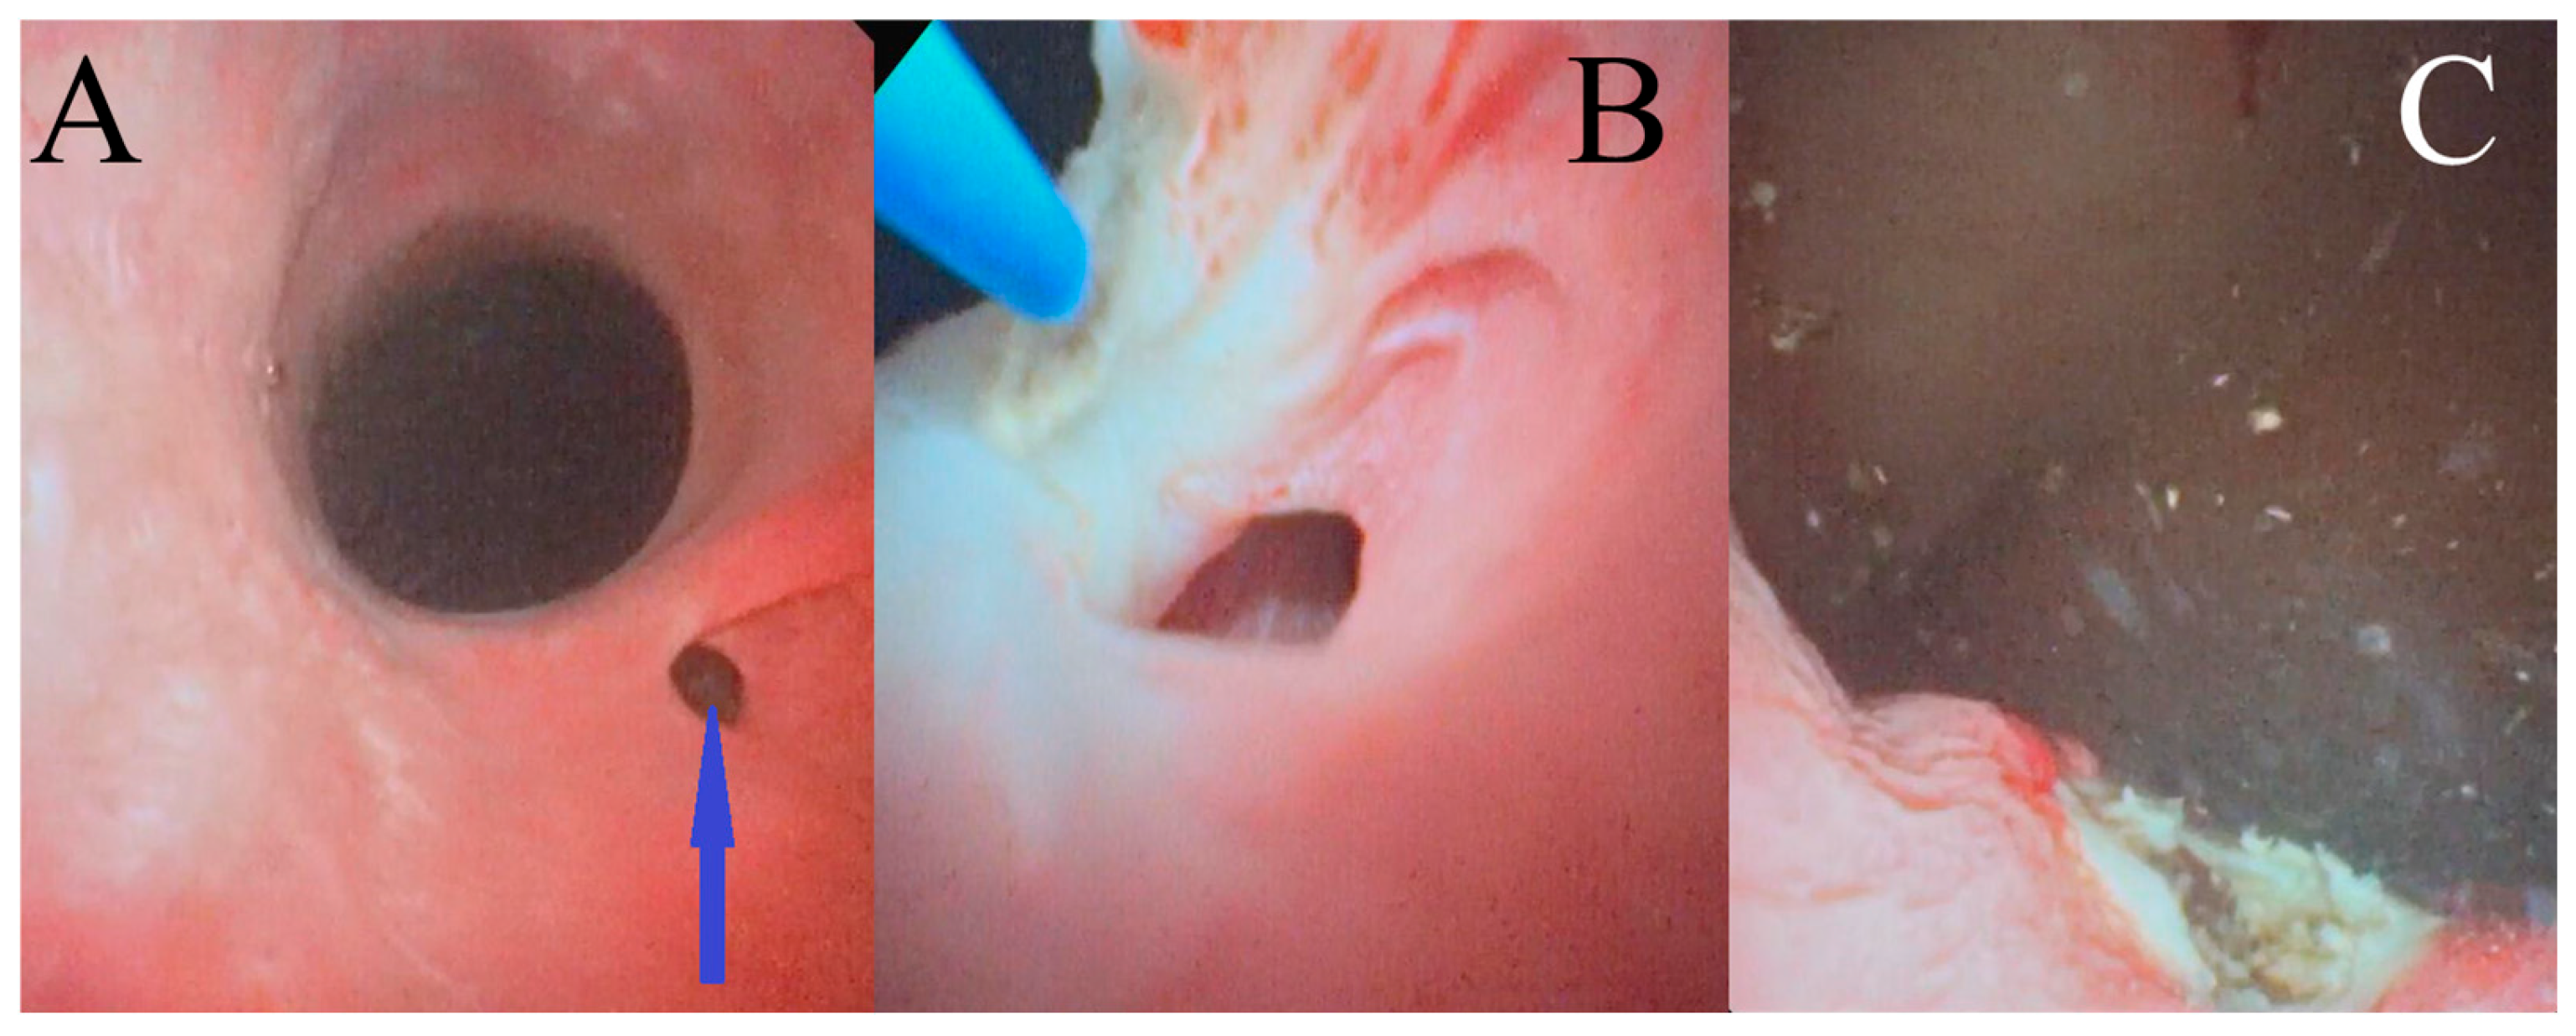

2.4. Cystoscopically Guided Laser Ablation in Male Dogs

Male dogs were placed in a right-hand laterally recumbent position. The skin around the penis was scrubbed and disinfected with chlorhexidine solution, and the preputium was rinsed with non-alcohol iodine solution. After sterile surgical drapes were placed, a flexible cystoscope (2.8 mm, Hawk, Zhejiang, China) was passed through the urethral orifice in a retrograde manner, utilizing manual saline irrigation (0.9% NaCl) solution (Figure 3A). The laser fiber (272-μm Hol:YAG) was introduced into the flexible cystoscope’s working channel and guided into the ureteral opening. In order to correctly angle the laser’s fiber tip toward the ureter’s medial wall, the cystoscope was deflected toward the urethral lumen, ensuring that the lateral wall was avoided. Transection of the medial ureter wall was then performed by using the Hol:YAG laser in a pulsating manner (Figure 3B). This procedure was considered complete once the ureterovesicular junction was within the lumen of the bladder (Figure 3C).

Figure 3. Cystoscopic images of an intramural ectopic ureter in a male dog: (A) the ectopic ureter opening into the urethra, indicated by the arrow; (B) image captured during cystoscopically guided laser ablation of the ectopic ureter; and (C) image captured after cystoscopically guided laser ablation of the ectopic ureter wall.